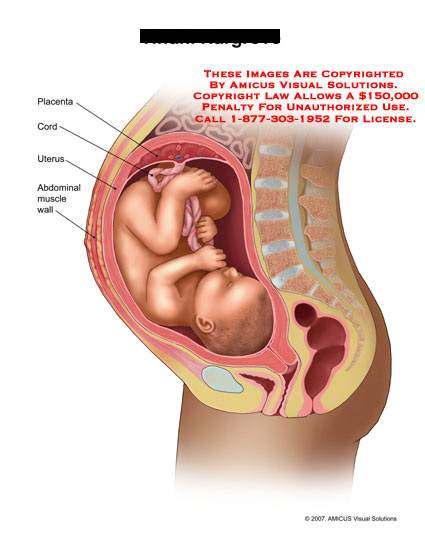

Физиология беременности: строение органов

Раздел: Моменты озарения